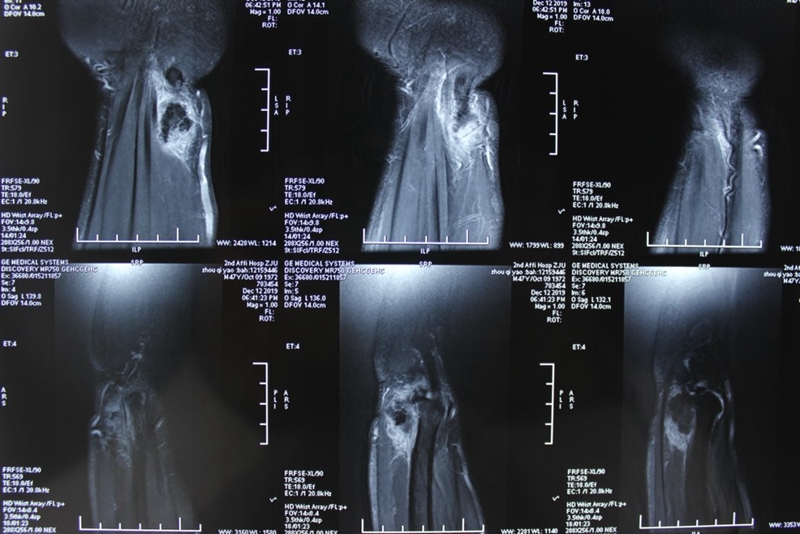

左腕关节核磁共振:左腕尺侧软组织占位